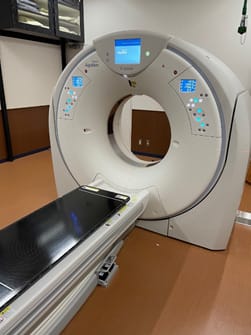

当院では、フィリップス社製Brilliance iCT Elite 256とキヤノン社製Aquilion 64の2台が稼働しています。

2020年1月より、当院では患者さまの画像診断の向上を目的としてフィリップス社製全身用コンピュータ断層撮影装置(CT装置)Brilliance iCT(ブリリアンス・アイ・シーティ)を導入しました。

新装置の特徴として、

0.27秒の高速回転により、従来の心臓CTでは検査が困難であった不整脈、高心拍、心拍変動の症例にも対応して撮影することができます。

256スライスによるワイドエリア化により、全身を約3秒程度で撮影することができます。高速スキャンと高画質を両立するとともに、患者さまの息止め時間が大幅に短くなります。手術前の検査では、手術支援画像としてさまざまな3次元画像を作成することで、形態の把握や手術計画に利用しています。

フィリップス独自の逐次近似応用再構成技術iDose4により、検査の目的・部位・撮影条件など必要に応じてノイズ低減ができ、さまざまな臨床応用を可能とします。医療被ばく低減施設として、高画質な画像をより低い被ばく線量で撮影することができます。

全く新しい画像再構成法O-MAR(Metal Artifact Reduction for Orthopedic implants)により、金属による画像への影響を抑制した診断に有用な画像を迅速に提供します。